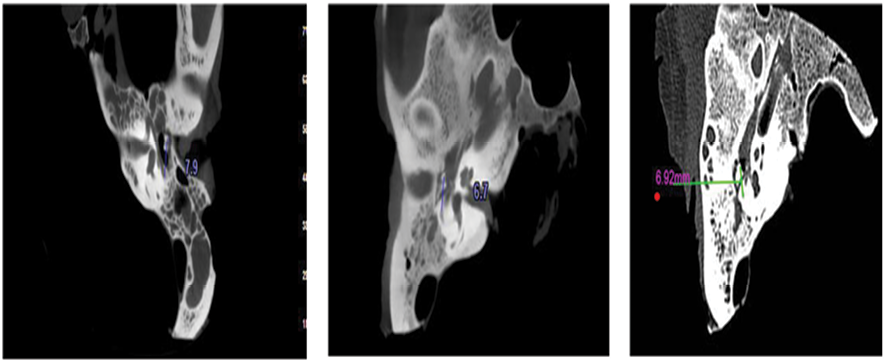

CBCT images were evaluated by a board-certified oral and maxillofacial radiologist, while MDCT images were assessed by a general radiologist, both using a 14-inch ASUS LED monitor (1920 × 1080 resolution) in a semi-darkened, controlled viewing environment. For each image, the distances between the round window and the oval window, and between the incus and the facial nerve, were measured using the digital ruler tool available within the respective CT and CBCT software platforms (see Figure-1 for illustration).

Figure 1. MDCT image (right), Low-resolution CBCT (middle), and High-resolution CBCT (left) for measuring the distance of the incus from the facial nerve